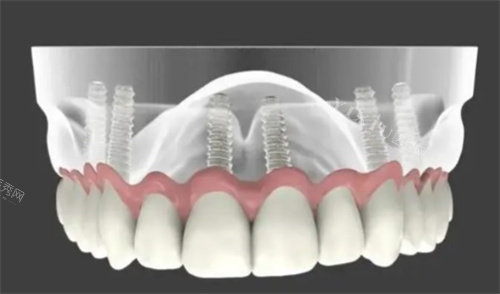

单颗上门牙缺失是种植修复的理想适应症之一。相比传统修复方式,种植牙不需要磨削邻牙,能够更大限度保存健康牙体组织。对于多颗相邻上门牙缺失的情况,在骨量允许的条件下,种植修复可以避免使用大跨度桥体,减少修复体对牙龈组织的压迫。全口牙列缺失患者在上颌前牙区植入种植体,能显著提高全口义齿的固位力和稳定性。

三维位置正确性对美学结果至关重要。种植体植入的深度、角度和位置需要精细规划,既要确保良好的生物力学分布,又要为修复体提供理想穿龈轮廓。现代导板技术有助于实现精密植入,但医生经验仍是成功的关键因素。

详细的影像学检查不可或缺。锥形束CT能够明确评估剩余骨量、骨密度及重要解剖结构的位置关系。对于复杂病例,智能化模拟技术可以帮助规划种植体三维位置。常规口腔检查需要评估邻牙和咬合状况,存在问题的牙齿需要先要进行治疗。

治疗方案的制定需要综合考虑多方面因素。根据缺牙数量、骨量条件、美观要求等,医生会提出包括种植体数量、直径、长度、修复方式等在内的详细计划。患者应充分了解治疗步骤、时间安排、费用构成及可能的风险,做出知情选择。